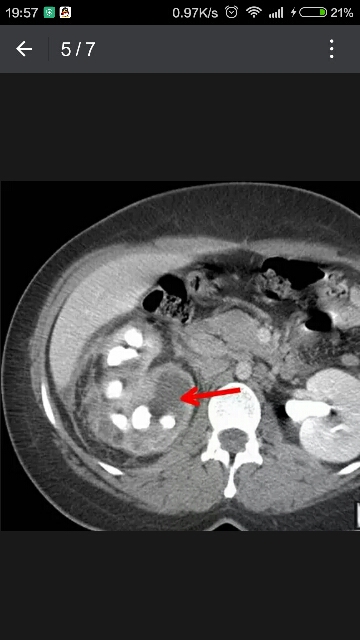

57岁糖尿病患者,腹痛、发热。

2.CT为可供选择的检查方法

(1)不均匀、无强化肿块

(2)肾积水

(3)正常肾实质破坏

(4)80%病例可见鹿角形结石

可为小钙化

(5)肾外侵犯